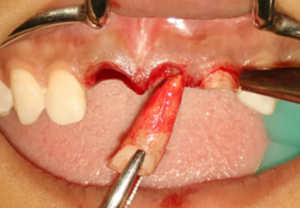

(2)即刻種植、即刻臨時修復(fù)。術(shù)中不翻瓣微創(chuàng)拔除牙根,牙槽 窩骨壁完整。在多級導(dǎo)板輔助下完成種植窩洞制備,植入Bego柱形種植 體,型號分別為:上頜右側(cè)中切牙位點4.1mm×15mm、上頜左側(cè)中切牙 位點?3.75mm×15mm、上頜左側(cè)側(cè)切牙位點3.25mm×15mm,扭矩均為 35N·cm。種植體與唇側(cè)骨壁間隙約2mm,植入Bio-Oss®Collagen骨膠 原。戴入橋用鈦臨時基臺,臨時冠就位順利,自凝樹脂口內(nèi)粘接后適當(dāng)修整 外形,充分磨光,調(diào) 至正中 、前伸 和側(cè)方 與對頜牙均無接觸。術(shù)后 根尖片顯示種植體位置、方向良好。

圖7 不翻瓣微創(chuàng)拔牙

圖8 導(dǎo)板輔助下備洞